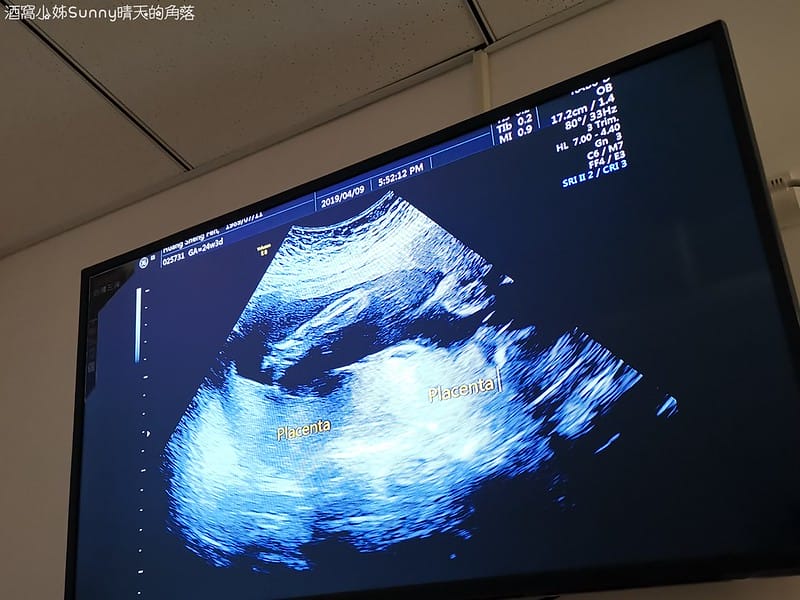

8. 胎盤位置

▼所以醫生在解釋的時候我們大概可以聽懂7~8成(下圖是胎盤,但不說一般人應該很難看懂吧!)